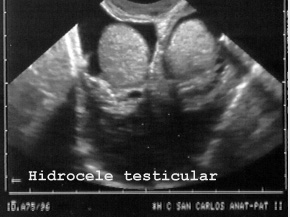

testículo (Fig 73),

73HIDROC.JPG (24078 bytes)

Fig 73

piel y tejidos subcutáneos son fáciles de descubrir, punzar y diagnosticar mediante microscopía y como el resto de los órganos y estructuras no mencionados no presentan caracteres muy peculiares en la ecopsia respecto de los caracteres observados en la ecografía en vida por lo que no exponemos ejemplos.